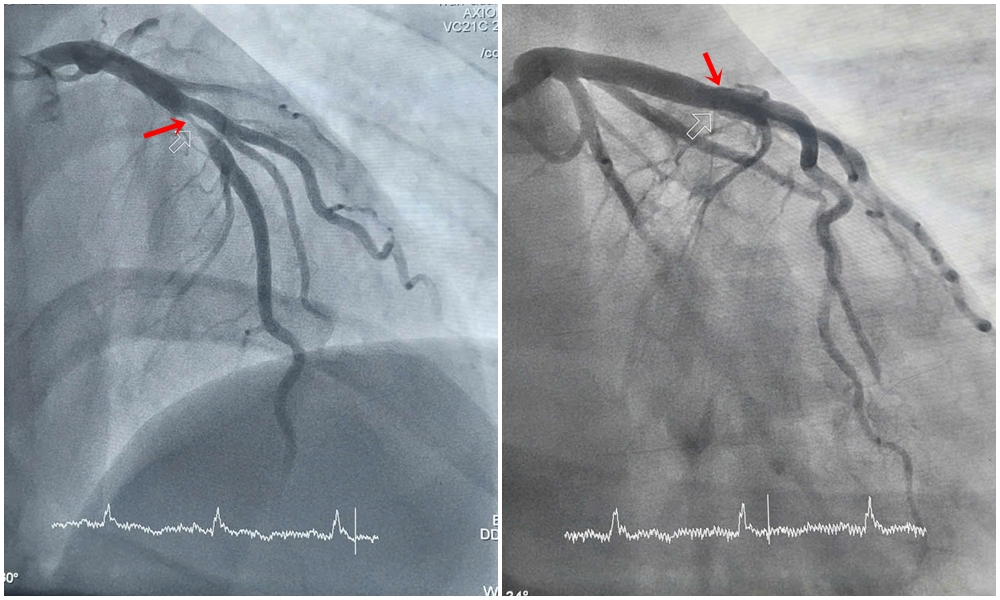

Hình ảnh hẹp tắc động mạch liên thất trước của bệnh nhân H. được can thiệp tái thông.

Kết quả chụp mạch vành cho thấy động mạch liên thất trước – một trong những nhánh quan trọng nhất nuôi dưỡng cơ tim bị tổn thương nặng, hẹp khít tới 99%. Trước tình huống nguy kịch, các bác sĩ khoa Phẫu thuật và Can thiệp Tim mạch đã nhanh chóng đặt stent nhằm tái thông máu nuôi tim, giúp người bệnh thoát khỏi tình trạng nguy hiểm.